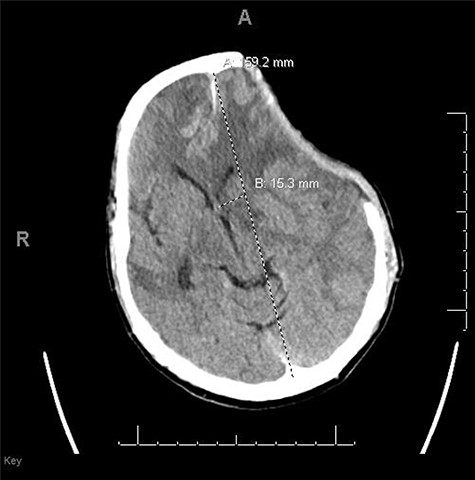

He had a significant recovery, to the point where he was awake with mild right paresis. He was following commands briskly but remained nonverbal. On hospital day 26, he developed neurological deterioration with decreased mental status and worsening right hemiparesis. Clinical examination noted pronounced new indentation of his hemicraniectomy flap site. CT head showed a rightward shift away from the craniectomy site and impending herniation (Fig. 4).

CT head POD26 from craniectomy demonstrating findings consistent with SSFS.